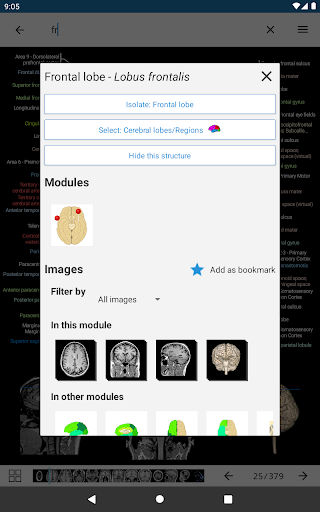

- Ketuk label untuk menampilkan struktur anatomi

*Peningkatan tampilan detail bagian anatomi untuk memudahkan identifikasi dalam gambar modul saat ini dan modul lainnya.

-Dalam tampilan detail struktur anatomi , pin sekarang menunjukkan struktur terkait di semua gambar yang ada

Juga ketuk langsung pada gambar untuk menavigasi ke gambar yang disajikan dalam modul itu

- "Filter oleh", dalam tampilan detail Anda sekarang dapat menyaring gambar yang mengandung struktur anatomi oleh modalitas